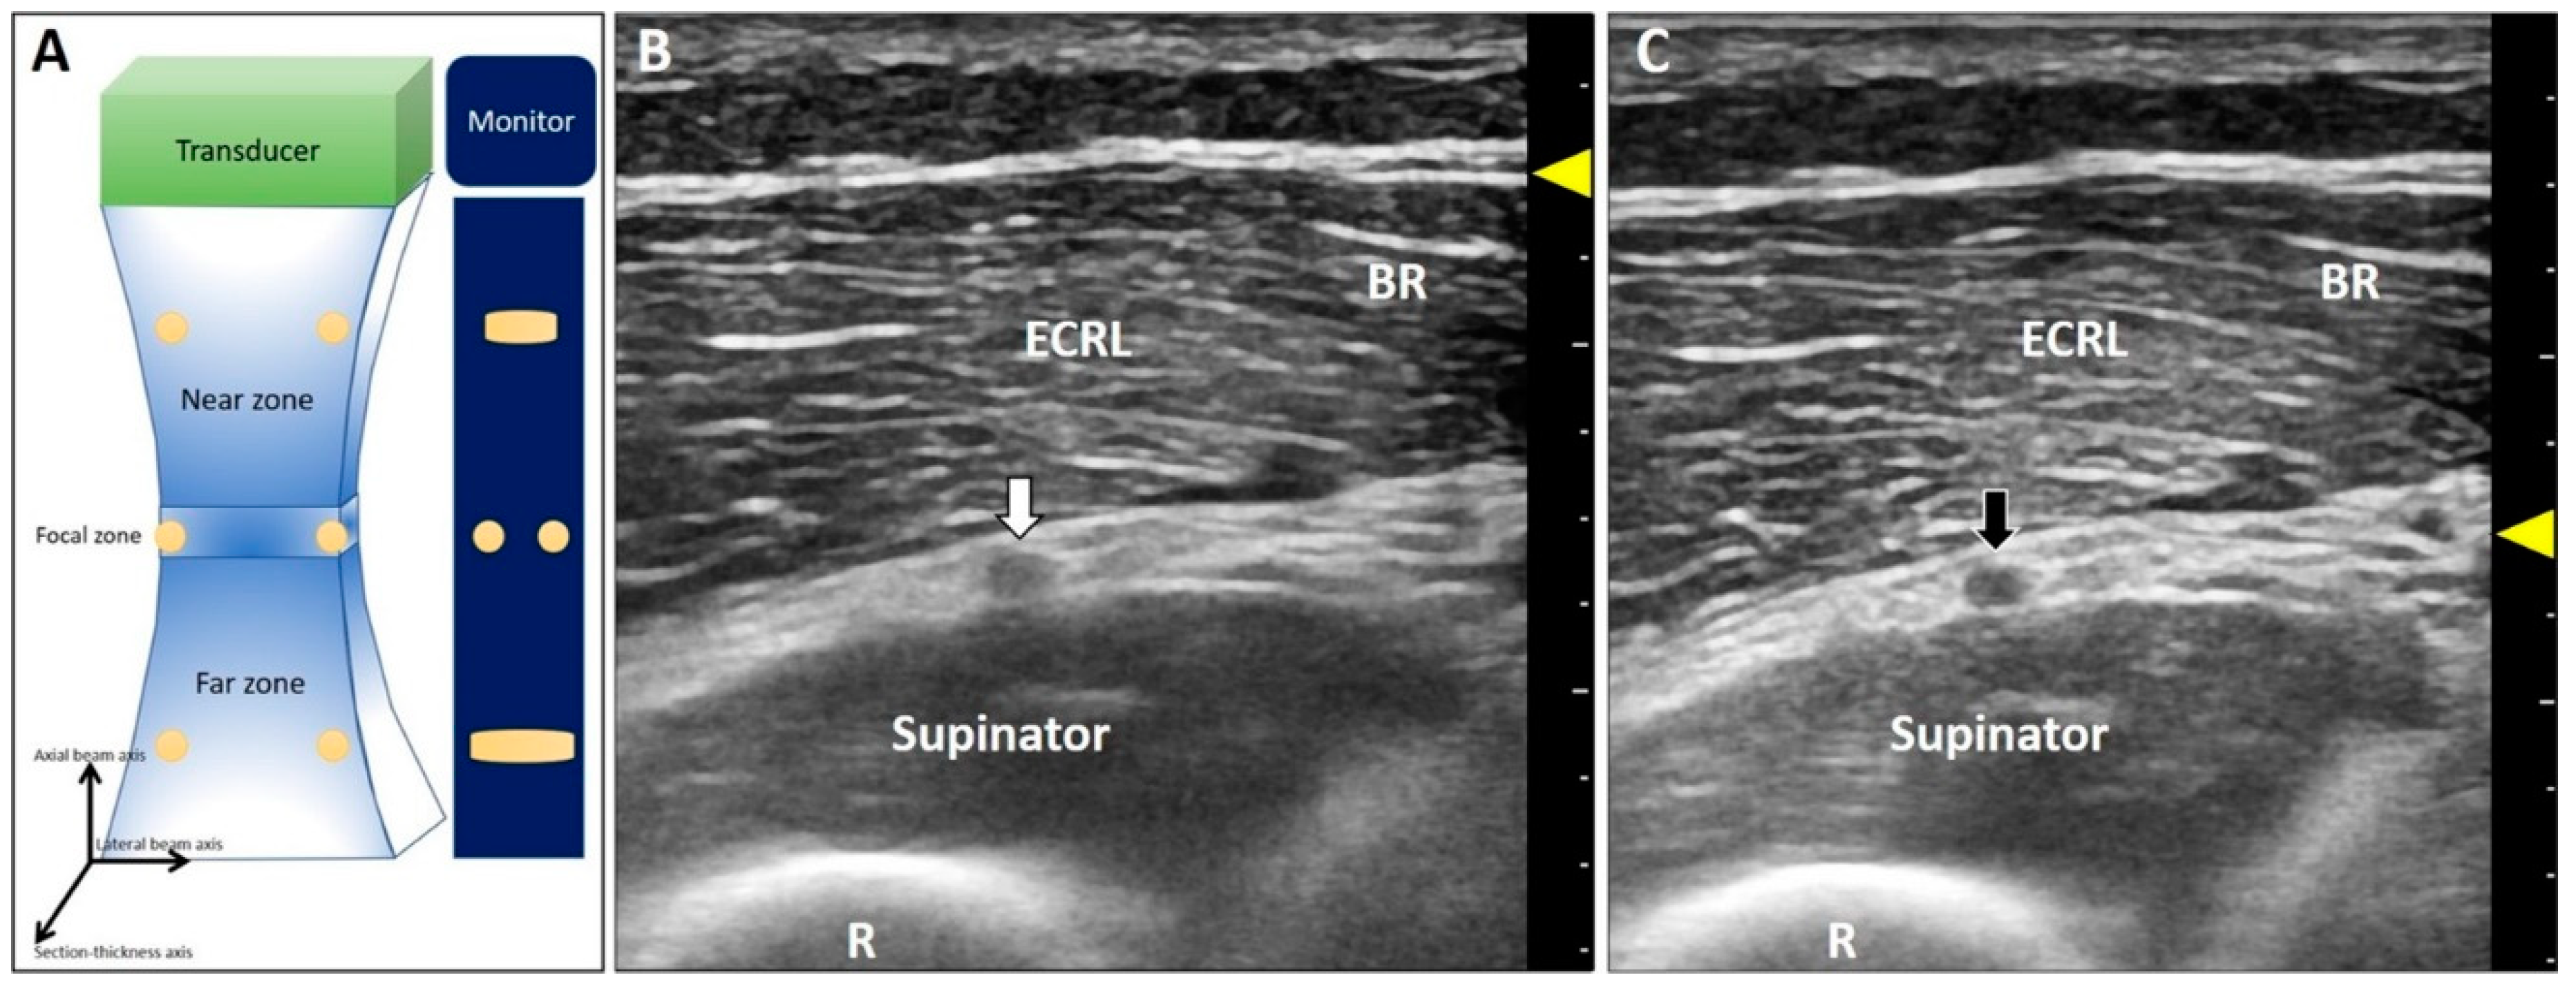

This artifact is also known as beam-width artifact and is associated with lateral resolution and section thickness of the US beam [14]. Beam width (Figure 2A) and section thickness are the narrowest in the focal zone. Hence, the resolution for differentiating two objects perpendicular to the propagation of US waves is the highest. If the distance between two adjacent targets is smaller than the width of the US waves, their images will be overlapped on the monitor. Accordingly, in the near or far zones, the resolution will decline because of the divergence of the US beams (Figure 2A).

Figure 2.

The US beam width is the narrowest at the focal zone with the best lateral resolution of two objects perpendicular to the beam (A). The deep radial nerve is blurred at the far zone (B) and becomes clearer when the focus has been set at the same depth as the nerve (C). White arrow: the blurred image of the deep radial nerve due to the improper location of the focal zone; black arrow: the clear image of the deep radial nerve after adjustment of the focal zone; yellow arrowheads: focal zone. ECRL: extensor carpi radialis longus muscle; BR: brachioradialis muscle; R: radius.

2.1.2. Clinical Examples

Poor resolution of a lesion makes it indistinguishable from the normal structure. For instance, concerning nerve entrapment [15], measurement of the cross-sectional area is crucial for diagnosis. If the focal zone is not placed at the right depth, the epineurium will appear blurred [16]. Another example is imprecise differentiation of the neural fascicle of the deep radial nerve from the connective tissues in the supinator tunnel when the target/focus is placed at the far field (Figure 2B). Once the focus is tuned to the suitable depth, the epineurium of the nerve is clearly presented in contrast to the adjacent tissues (Figure 2C).